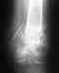

Мне 32. Прошлым летом был сложный втутрисуставной осколочный перелом дистального отдела большеберцовой кости. Выполнили открытую репозицию (поставили две пластины и 14 винтов).

Осенью начал ходить. Было ощущение, что когда наступаю на ногу, нога в суставе "как-бы разъезжается в стороны". Приблизительно к новому году эти ощещения прошли, но примерно в это же время (может быть совпало) начало болеть ахилово сухожилие и какие-то или сухожилия или связки "во впадинах" по бокам от него. Тогда же появились щелчки (иногда болезненные) в районе ахилового сухожилия, при движениях в суставе без нагрузки. На носок ногу нагрузить не могу -- больно в районе ахилова сухожилия и в этих "впадинах". Если ногу в колене чуть согнуть и подать колено вперед, тогда стоять на носке получается (хоть и больно), в этом положении стопа оказывается почти перпендикулярна голени. Иногда пробую крутить велотренажер, после сеанса с совсем небольшой нагрузкой несколько дней сухожилия болят очень сильно. На всякий случай: через неделю после операции умудрился удариться (почти наступить) ногой, был в лангете с эластичным бинтом. По словам хирурга это вызвало появление щели, которую видно на снимке "сбоку". По моим догадкам сместился вперед и вверх передний отломок, "испортив" поверхность сустава. Две недели назад сняли металлоконструкции. В аспекте, на который тут жалуюсь, лучше не стало. Здесь есть снимок (еще с металлоконструкциями): http://dl.dropbox.com/u/58743910/Published/mamitko2011.JPG Здесь есть МСКТ (осторожно, 340 MB !) http://dl.dropbox.com/u/58743910/Published/mamitko_ankle.rar Буду благодарен за любые комментарии. В тайне еще надеюсь заниматься спортом.